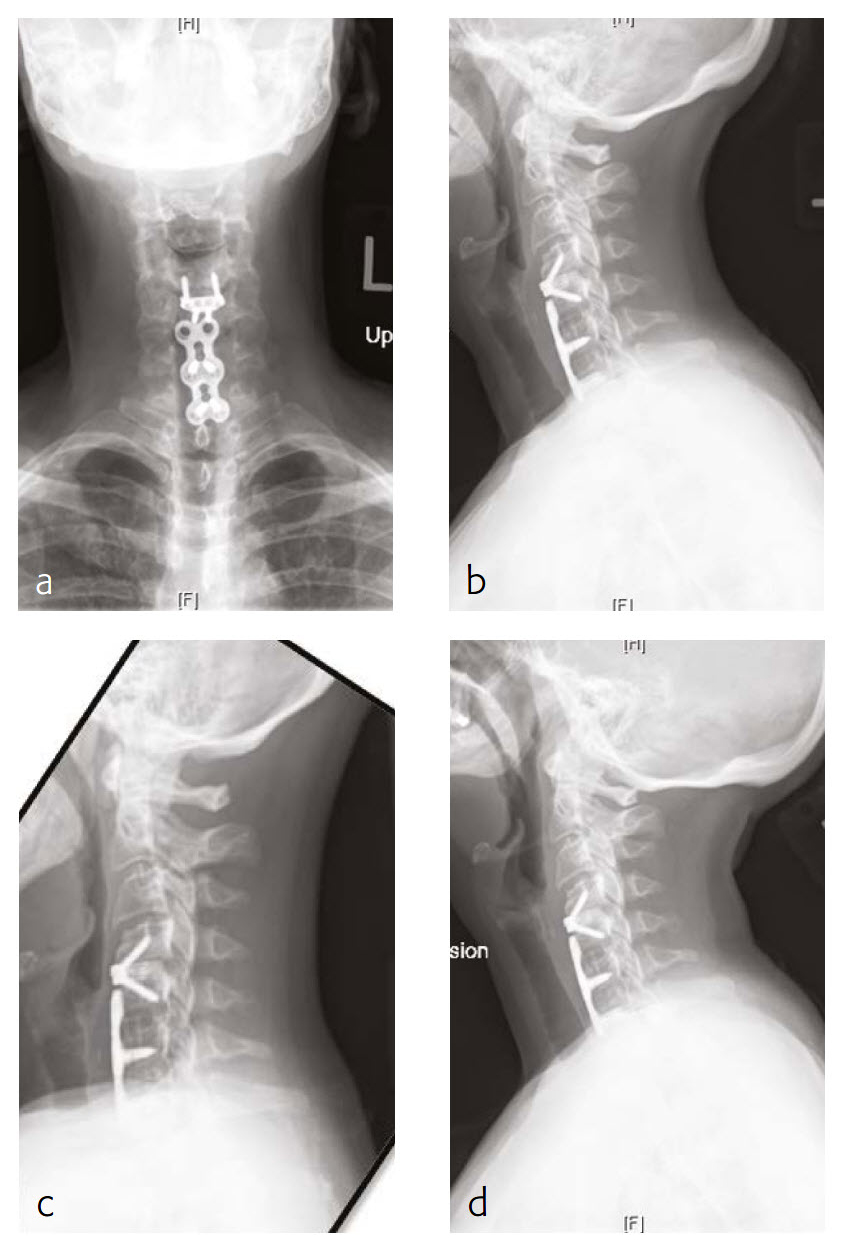

Case 3: A 46-year-old woman with neck pain and upper extremity paresthesia

A 46-year-old woman presented with one-year history of neck pain, upper extremity paresthesia, weakness, and subjective numbness (Fig 5). Her right upper extremity was worse than her left, with loss of function and debilitating pain. She described cramping in her upper extremities without etiology and without alleviating factors.

She had not been responsive to anti-inflammatory medications nor other nonoperative treatment including physical therapy. She had trouble with many of her activities of daily living due to breaks that must be taken due to her pain, as well as the inability to do certain things like open jars due to weakness.

Musculoskeletally, she had no obvious deformity in any of her extremities. Her bilateral upper extremities had strength testing of 5/5 in shoulder abduction, elbow flexion/extension, wrist extension/flexion, and finger abduction/flexion. Bilateral lower extremities showed 5/5 strength with hip flexion bilaterally, as well as bilateral 5/5 strength knee extension, dorsiflexion, plantar flexion of the ankle, and firing EHL.

She had sensation that is intact in all dermatomes. She had no pathological reflexes and no clonus. There was normal tandem gait.

Review of the patients outside imaging showed congenital stenosis of the cervical spine, as well as multilevel disk disease and concomitant acquired stenosis in the foramen of C4-C5, C5-C6, and C6-C7 where it was at its most significant level.

Follow-up (4 months)

At the 4-month follow-up, the patients symptoms were largely resolved and she has been able to return to work (Fig 6). She was very satisfied with her outcome. made significant progress in terms of his left upper extremity range-of-motion and strength.